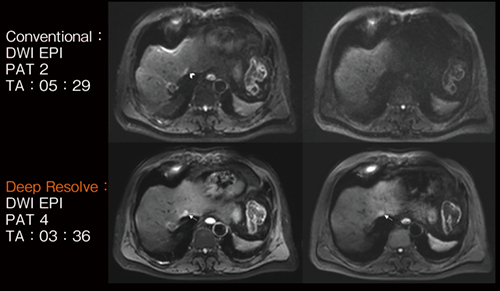

Deep Resolveのもう1つの拡張として,シングルショットEPIによる拡散強調画像(DWI)の撮像にも適用ができるようになった。Deep Resolveの活用により,高いPAT factorの撮像が可能になるため,EPIによるDWIの撮像で問題となる歪みを大幅に低減できる。また,SNRも向上するため,歪みの低減と合わせて病変部の視認性が向上する(図5)。なお,ファントムを用いた検討や頭部,腹部,乳房などの複数部位の検討において,Deep Resolveの画像再構成はADC値に影響を与えないことが確認されている6)。以上のように,Deep Resolve DWIによる画質改善は,より確信度の高い診断を支援することが期待できる。

図5 Deep Resolve DWIの画像比較

従来のDWI(上段)と比較して,Deep Resolve DWI(下段)では,歪みが低減し,かつ加算回数を減らして撮像時間を短くしてもSNRが高いことがわかる。